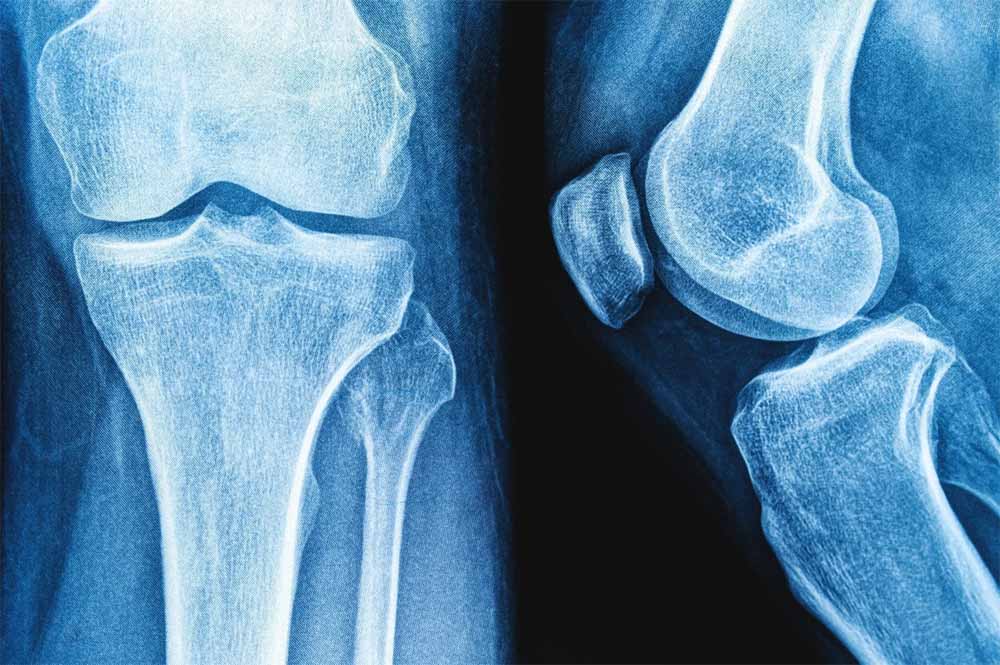

हड्डी के फ्रैक्चर और रोगों का इलाज अब प्रोटीन रिसर्च से संभव – NIT की खोज

राष्ट्रीय प्रौद्योगिकी संस्थान (एनआईटी) राउरकेला के शोधकर्ताओं ने मानव शरीर में पाई जाने वाली प्राकृतिक शर्करा जैसे अणु हड्डियों के निर्माण और मरम्मत के लिए जिम्मेदार प्रोटीन, बोन मॉर्फोजेनेटिक प्रोटीन-2 के व्यवहार को कैसे प्रभावित कर सकती है? इसका पता लगाया है।

प्रतिष्ठित पत्रिका बायोकैमिस्ट्री में प्रकाशित इस शोध के निष्कर्षों का उपयोग हड्डी और उपास्थि पुनर्जनन के उन्नत उपचार, बेहतर इम्प्लांट और अधिक प्रभावी प्रोटीन-आधारित दवाओं के विकास में किया जा सकता है। प्रोटीन मनुष्य के शरीर में विभिन्न कार्य करते हैं। टिश्यू के निर्माण और रासायनिक प्रतिक्रियाओं में सहयोग देने से लेकर कोशिकाओं के बीच संकेतों के रूप में कार्य करने तक बड़ी जिम्मेदारी निभाते हैं।

हालांकि सर्वोत्तम उत्पादकता के लिए इनका त्रि-आयामी आकृतियों में सटीक मुड़ना या खुलना आवश्यक है। प्रोटीन क्यों और कैसे खुलते हैं? यह समझना जीव विज्ञान का एक प्रमुख लक्ष्य है। इसका प्रभाव चिकित्सा, जैव प्रौद्योगिकी और ड्रग डिलिवरी पर पड़ता है। इस संदर्भ में हड्डी और उपास्थि के निर्माण, चोटों को ठीक करने और स्टेम कोशिकाओं को अस्थि-निर्माण कोशिकाओं में परिणत करने में बीएमपी-2 महत्वपूर्ण भूमिका निभाता है।